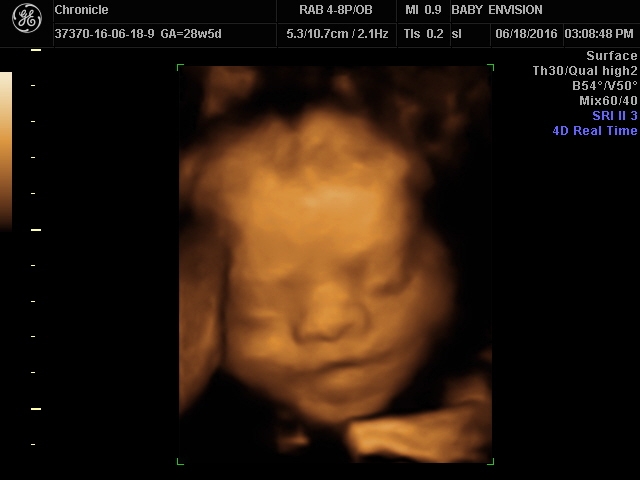

I gave his DH part of his bday present - a trip to the 3D & 4D scan and we were able to see features of our little love. She, so far, is looking more like her momma.